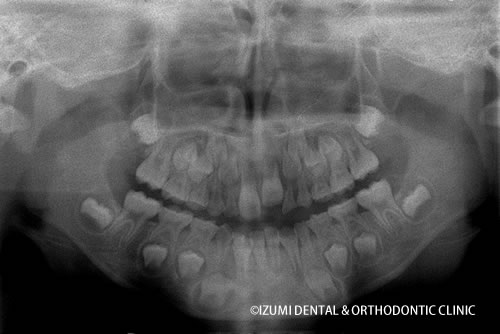

以下のエックス線写真は、7歳(確認要)の女の子が最初に当院へいらした時のものです。

矯正開始前(7歳5ヶ月)

顎骨の比較

顎は大きくなり、歯の並び方が自然なカーブに変わっていったのがおわかりになるでしょう。

萌出前の永久歯たちがはえてこようと準備しています。